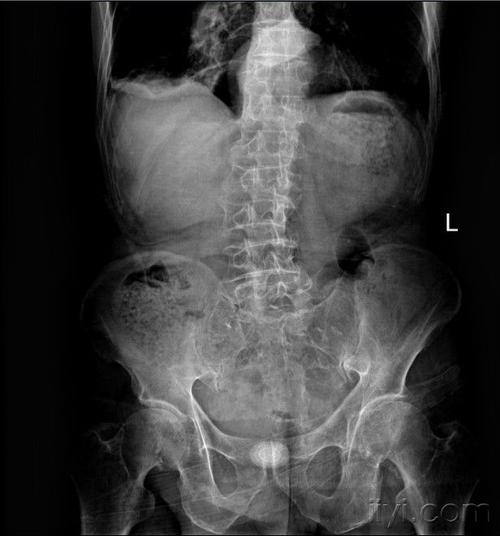

比较典型的腹部平片

腹部平片

腹部平片正常图片

腹部平片图

正常腹部平片

肠梗阻腹部平片图片

正常腹部立位平片图片

腹部平片气液平面

正常腹部x线平片图

腹部卧位平片

腹部x线平片

腹部立位片

腹部卧位片

腹部平片气液平面图片